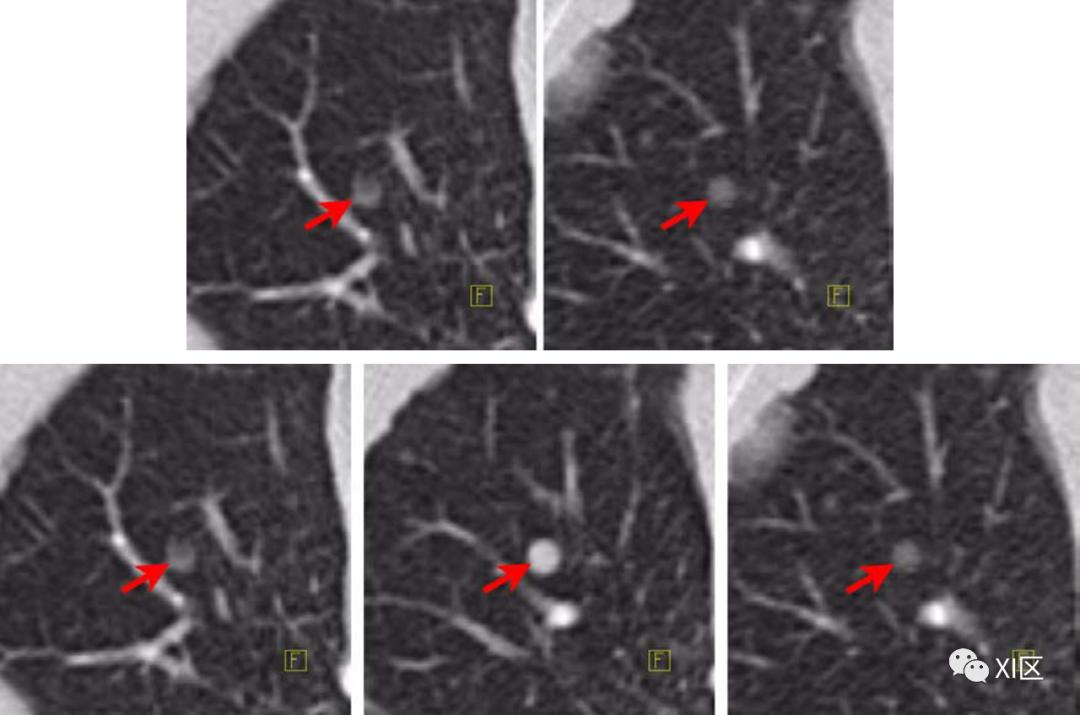

相同层厚的两组图像,使用IVR重建(下排)可以更清晰地观察肺结节的细节信息。